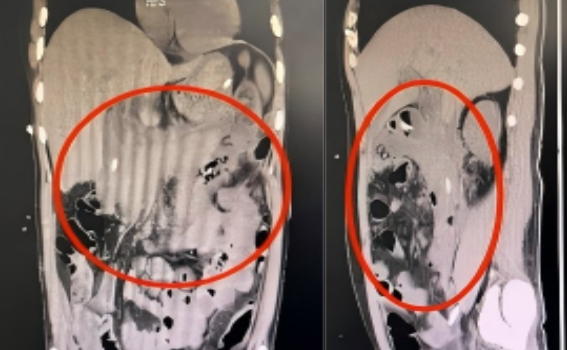

明确诊断: 完善相关影像学检查了解腹部情况,CT 检查显示胰腺明显肿胀、形态失常,胰腺明显肿胀、形态失常,胰周渗出明显,符合急性坏死性胰腺炎。

尽管重症医学科团队全力救治,反复多次予调整抗感染方案,持续坏死组织冲洗,病魔仍在反扑:刘先生仍持续高热,尿少,腹腔压力高,胃肠功能障碍,营养功能差。3 月中旬复查 CT 显示胰腺周围稍高密度灶较前稍增多,两侧结肠旁沟密度灶较前减少。

在重症医学科中西医结合治疗下,刘先生的病情迎来了转机:他的神志逐渐清醒,体温稳步下降至正常,腹部变软,呼吸改善,感染指标持续下降,肾功能好转,尿量增加,复查腹部 CT 可见胰周渗出较前明显减少。